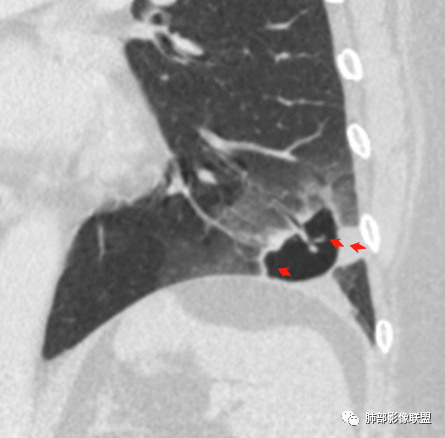

1、左肺下叶外基底段不规则囊腔样病灶,囊腔内有条形影及血管穿行。

2、囊壁薄厚不均匀,稍显僵硬,有壁结节(对应边缘分叶等)、结节强化明显。

以上两条几乎将肺囊肿彻底排除在外,且高度怀疑新生物!

4、冠状位部分层面可见支气管在囊腔边缘截断。

本例囊腔性病灶尽管腔壁稍显僵硬,壁结节凸显,但女性患者,灶周明显磨玻璃晕,都强烈提示为囊腔性腺癌。